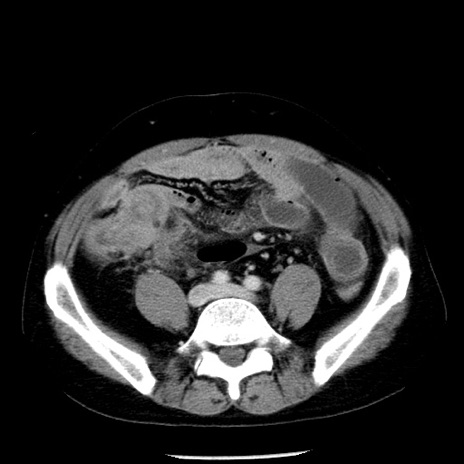

症例29(横断像)

【症例】40歳代男性

【現病歴】2日前から胃痛あり。徐々に周期的な激痛に変化した。本日になっても激痛があるため受診。

【身体所見】意識清明、BT 38-39℃台あり、腹部:膨満、やや硬、右下腹部に圧痛あり。

【データ】WBC 8500、CRP 23.26